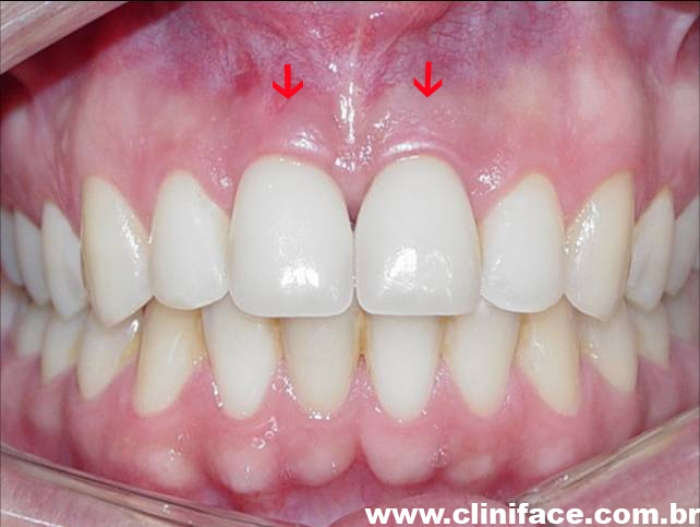

Próteses provisórias imediatas nos elementos 11 e 21